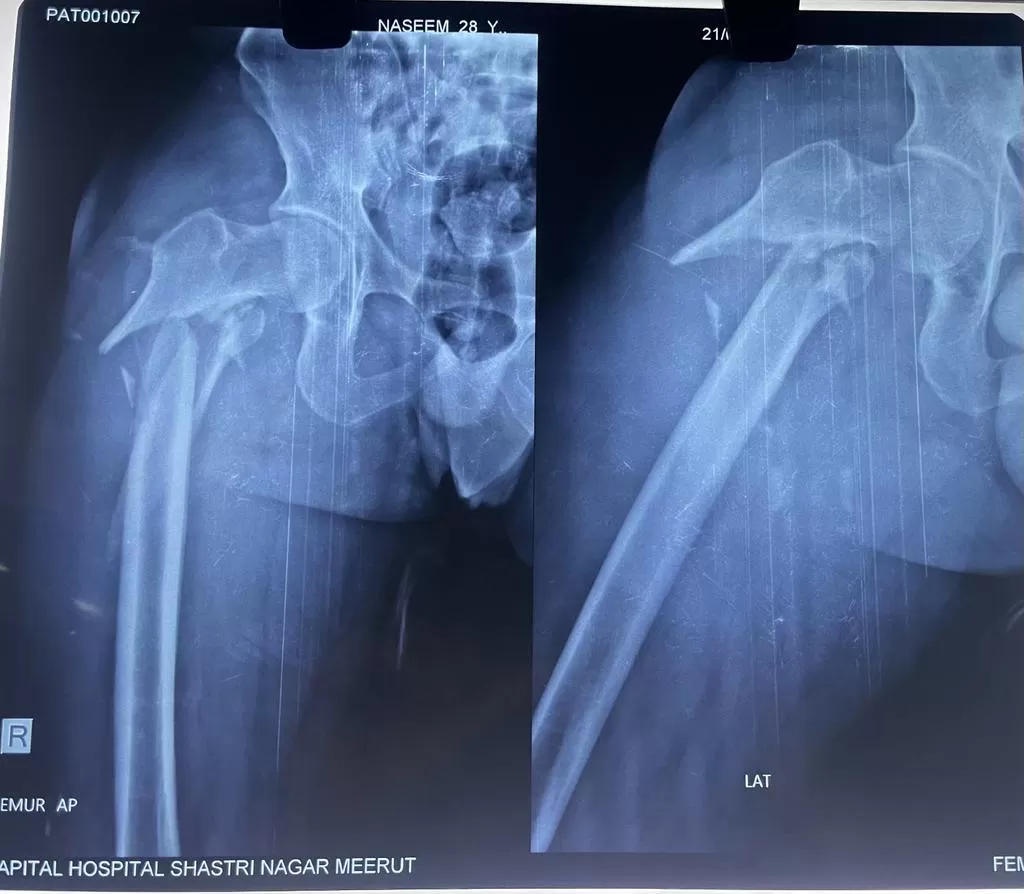

Mr. Naseem

Name: Mr. Naseem

Date of Operation: 8 Jan 2024

Age: 28 Years